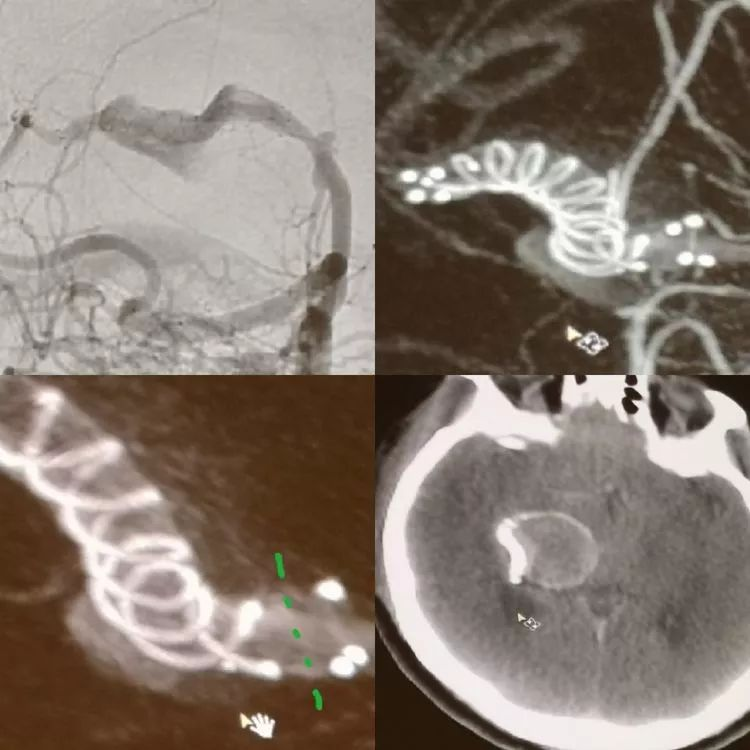

CASE 5 AN

-WEB是治疗分叉部动脉瘤的新武器

-WEB治疗复发的原因分析:一种解释是压缩造成的,wakhloo认为另外一个可能的原因是血栓的机化,机化的血栓可能牵拉WEB造成复发